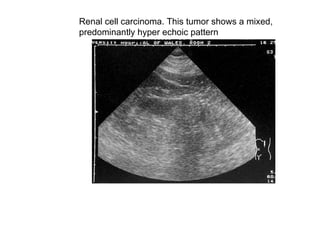

Renal cell carcinoma. This tumor shows a mixed,  predominantly hyper echoic pattern